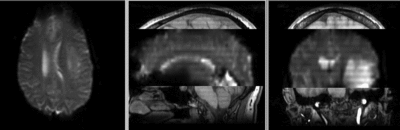

this is the fMRI baseline image, to be registered to the T1

Target Anatomical Ref. fMRI

• moving: fMRI sequence of motor task (right hand clench) 2 x 2 x 4 mm, 128 x 128 x 19

• the fMRI contains acquisition-related distortions that can make automated registration difficult.

• the fMRI contains low tissue contrast, making automated intensity-based registration difficult.

unregistered unregistered

after rigid registration after rigid registration

after non-rigid registration after additional BSpline non-rigid registration